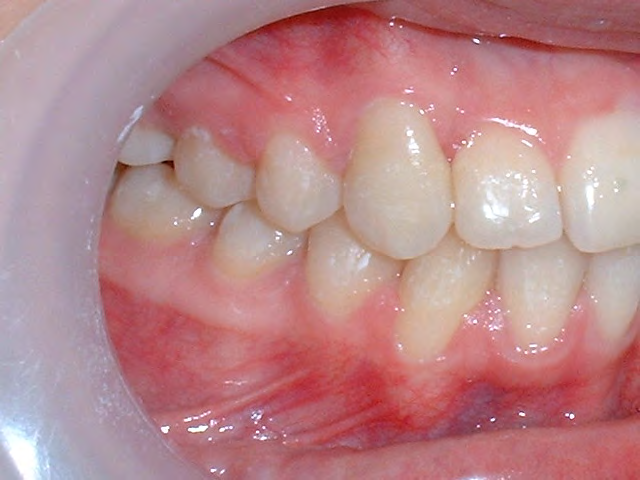

All of the patients below had been told they required extractions by orthodontists, some insisting that they could not be treated without extractions.

They were all treated without extractions, head gear or facemasks at Vakresmil and represent just a small sample of cases treated between 2004–2014.

Below are cases treated at Vakresmil without extractions within the last three years. The families had been told, “It is simply not possible for your child to be treated without extractions” by orthodontists. Judge for yourself if that was right or wrong.

The overall aim is to produce the best smile we can — a “beautiful smile”, if you will — without premolar extractions, headgear, facemasks or banded appliances. A smile that both the patient and we at Vakresmil can be proud of.